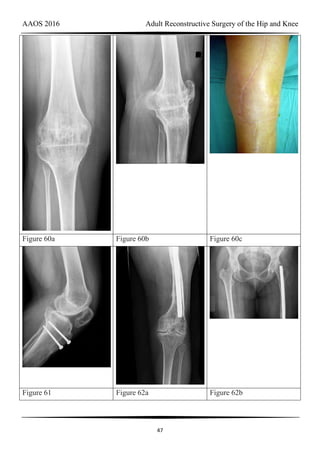

Figure 60a Figure 60b Figure 60c

Figure 61 Figure 62a Figure 62b

RESPONSES FOR QUESTIONS 58 THROUGH 62

Total knee arthroplasty (TKA) is performed to address each condition shown in Figures

58 through 62b. Which complication is most commonly associated with each image?

Question 60 of 200

Figure 60a through Figure 60c

PREFERRED RESPONSE: 2- Skin necrosis

Question 61 of 200

Figure 61

PREFERRED RESPONSE: 5- Anterior knee pain

Question 62 of 200

Figure 62a and Figure 62b

PREFERRED RESPONSE: 6- Malalignment

DISCUSSION

Figure 58 reveals a posttraumatic valgus deformity. Correction of valgus with lateral soft-

TKA to centralize the extensor mechanism. Figures 60a (anteroposterior [AP] view) and 60b

(lateral view) reveal a fused knee in full extension.

TKA after fusion is associated with multiple complications including skin necrosis,

infection, and instability. The skin is contracted because of limited knee motion and has

multiple scars (Figure 60c). Mobilization of the skin during and after knee arthroplasty can

place excess tension on the soft tissues, resulting in skin necrosis and infection. Treatment

consisting of prompt debridement and soft-tissue coverage, usually with medial gastrocnemius

muscle transposition, is required. Figure 61 shows a knee with prior tibial tubercle fixation

and marked patella infera. Shortening of the patellar ligament is associated with restricted knee

motion. This may necessitate more extensile exposure using tibial tubercle osteotomy or rectus

snip during TKA to obtain adequate surgical exposure. The inferior position of the patella can

cause impingement between the patellar component and tibial insert, resulting in anterior knee

pain. Restoring a more normal position of the patella may necessitate distal positioning of the

femoral component as well as tibial tubercle osteotomy with proximal recession of the

osteotomized tibial tubercle. Figures 62a (AP view of the distal femur) and 62b (AP view of

the proximal femur) show a posttraumatic deformity with a large retained intramedullary rod.

There is a varus distal femoral deformity that is not severe enough to necessitate extra-articular

corrective osteotomy. However, intramedullary hardware precludes use of conventional

intramedullary instrumentation, so computer navigation or patient-specific cutting guides will

be necessary to orient the bone cuts and avoid implant malalignment.